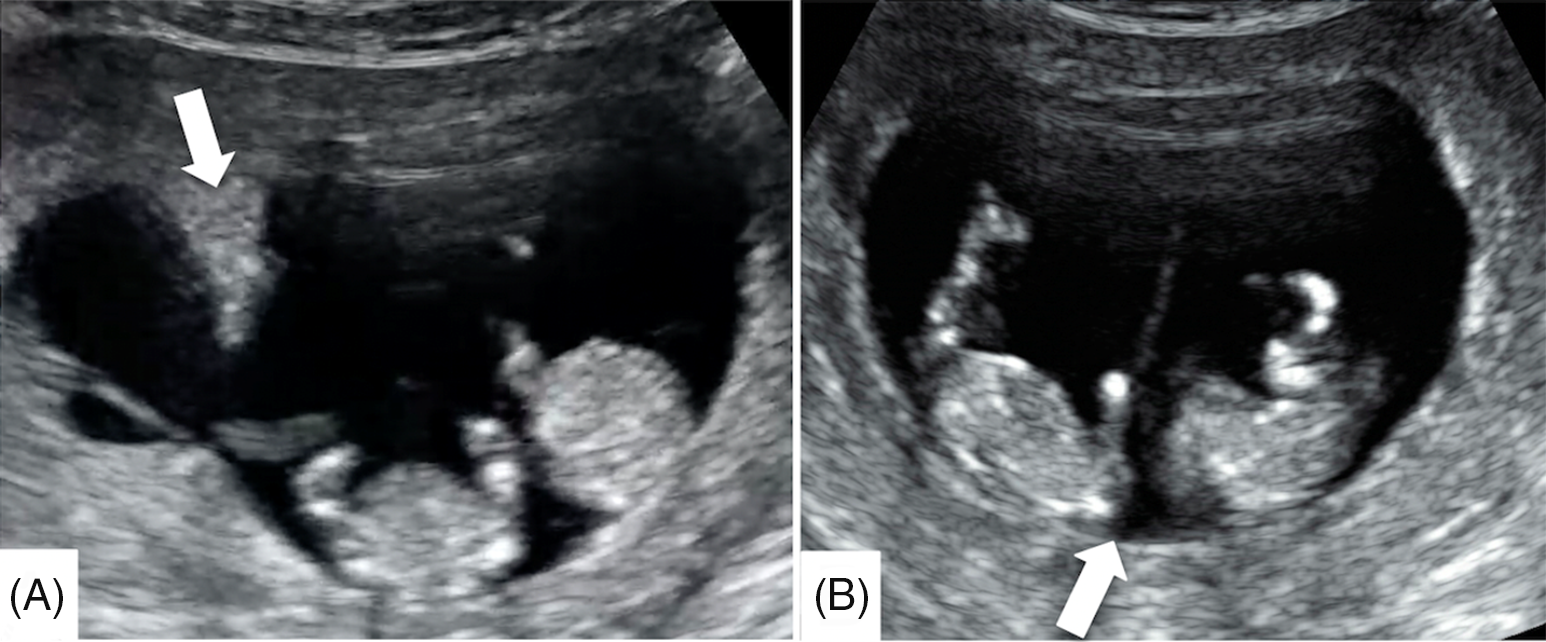

At 11 weeks’ gestation, an ultrasound image showed a lambda sign at one portion of the septum (Figure 3A) and a T sign at another portion (Figure 3B). This change suggested that the folded chorionic membrane had partially flattened.

Fig. 3. (A) One part of the septum with chorionic membrane folding shows a lambda sign (arrow) at 11 weeks’ gestations. (B) Another part of the septum without chorionic membrane folding shows a T sign (arrow).

The lambda sign, also called as the twin peak sign, is a triangular tissue projection extending from the base of the intertwin membrane consisting of chorionic tissue between two amniotic membranes (Finberg, Reference Finberg1992). A recent meta-analysis showed that the presence of the lambda sign was very sensitive and specific in predicting chorionicity during ultrasonography in the first trimester (Maruotti et al., Reference Maruotti, Saccone, Moriando and Martinelli2016). Generally, the presence of the lambda sign indicates a dichorionic twin pregnancy. In this case, ultrasonography performed at 9 weeks’ gestation detected the lambda sign on both sides of the base of the intertwin membrane and amniotic membrane swelling between the two chorionic membranes. This finding supports the concept that CMF can show the lambda sign and that the form of CMF can change during pregnancy. The difference in the lambda sign between dichorionic monoamniotic (DCDA) twin pregnancies and MCDA twin pregnancies is that the triangular tissue projection extending from the base of the intertwin membrane is followed by a relatively thick membrane to the other side in DCDA twin pregnancies, whereas the CMF in MCDA twin pregnancies does not follow chorionic membrane from the lambda sign and the thick chorionic membrane appears to be interrupted.

In the absence of chorionic tissue, the bottom of the intertwin membrane is composed of two amniotic membranes and it is called a ‘T sign’. A similar case has been reported of an MCDA twin pregnancy that showed lambda and T signs on the first-trimester ultrasonography (Galjaard et al., Reference Galjaard, Moerman, Corveleyn, Devlieger and Lewi2014). Histological examination of the intertwin membrane is characterized by coexistent monochorionic (amnion-amnion) and dichorionic (amnion-chorion-chorion-amnion) components, and such cases are classified as partial monochorionic/dichorionic twins (Chmait et al., Reference Chmait, Floyd and Benirschke2011; Galjaard et al., Reference Galjaard, Moerman, Corveleyn, Devlieger and Lewi2014; Lu et al., Reference Lu, Cheng, Law and Leung2018). The lambda sign is found at the part with CMF, and the T sign is found at the other part without CMF. The mechanism causing CMF is unknown, but this complication is probably rare. In this case, both the lambda sign and T sign coexisted at 11 weeks’ gestation, suggesting that CMF can be flattened over time, and ultrasonography can show both the lambda and T signs depending on the timing of examination and location of scanning.